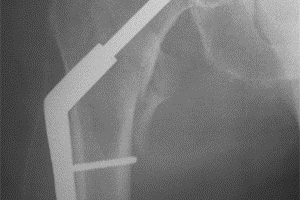

Den vanligste operasjonsmetoden ved trokantære brudd er en glideskrue (figur 4). Ved denne operasjonen skrues en stor skrue gjennom lårhalsen og opp i lårhodet. Skruen kan gli gjennom en plate som festes på utsiden av lårbeinet. Denne mekanismen sikrer at god kontakt i bruddet og dermed at bruddet gror raskere.

Trokantære brudd

En del av de trokantære bruddene regnes som ustabile. Disse bruddene opereres ofte i stedet med en margnagle som settes ned gjennom margkanalen i lårbeinet og som festes med skruer både gjennom lårhalsen og nederst gjennom lårbeinet (figur 5). Skruen(e) som går gjennom lårhalsen kan vanligvis gli gjennom naglen for å sikre god kontakt i bruddet og dermed at bruddet gror raskere.